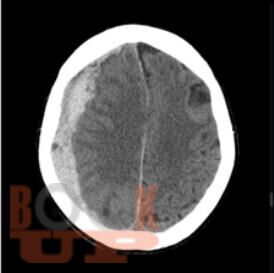

Интенсивная терапия внутричерепной гипертензии

Учебное пособие предназначено для ординаторов и слушателей курсов повышения квалификации по специальностям «Анестезиология и реаниматология», «Неврология», «Нейрохирургия». В настоящем учебном пособии освещены ключевые подходы к диагностике и оказанию помощи при внутричерепной гипертензии. Имеются тестовые задания и ситуационные задачи для самоконтроля знаний.